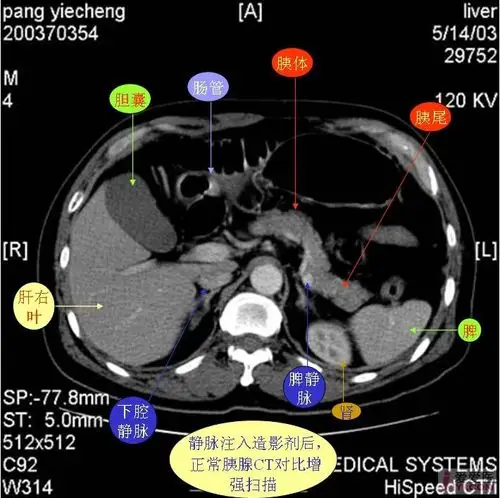

贴图一组胰腺ct图片